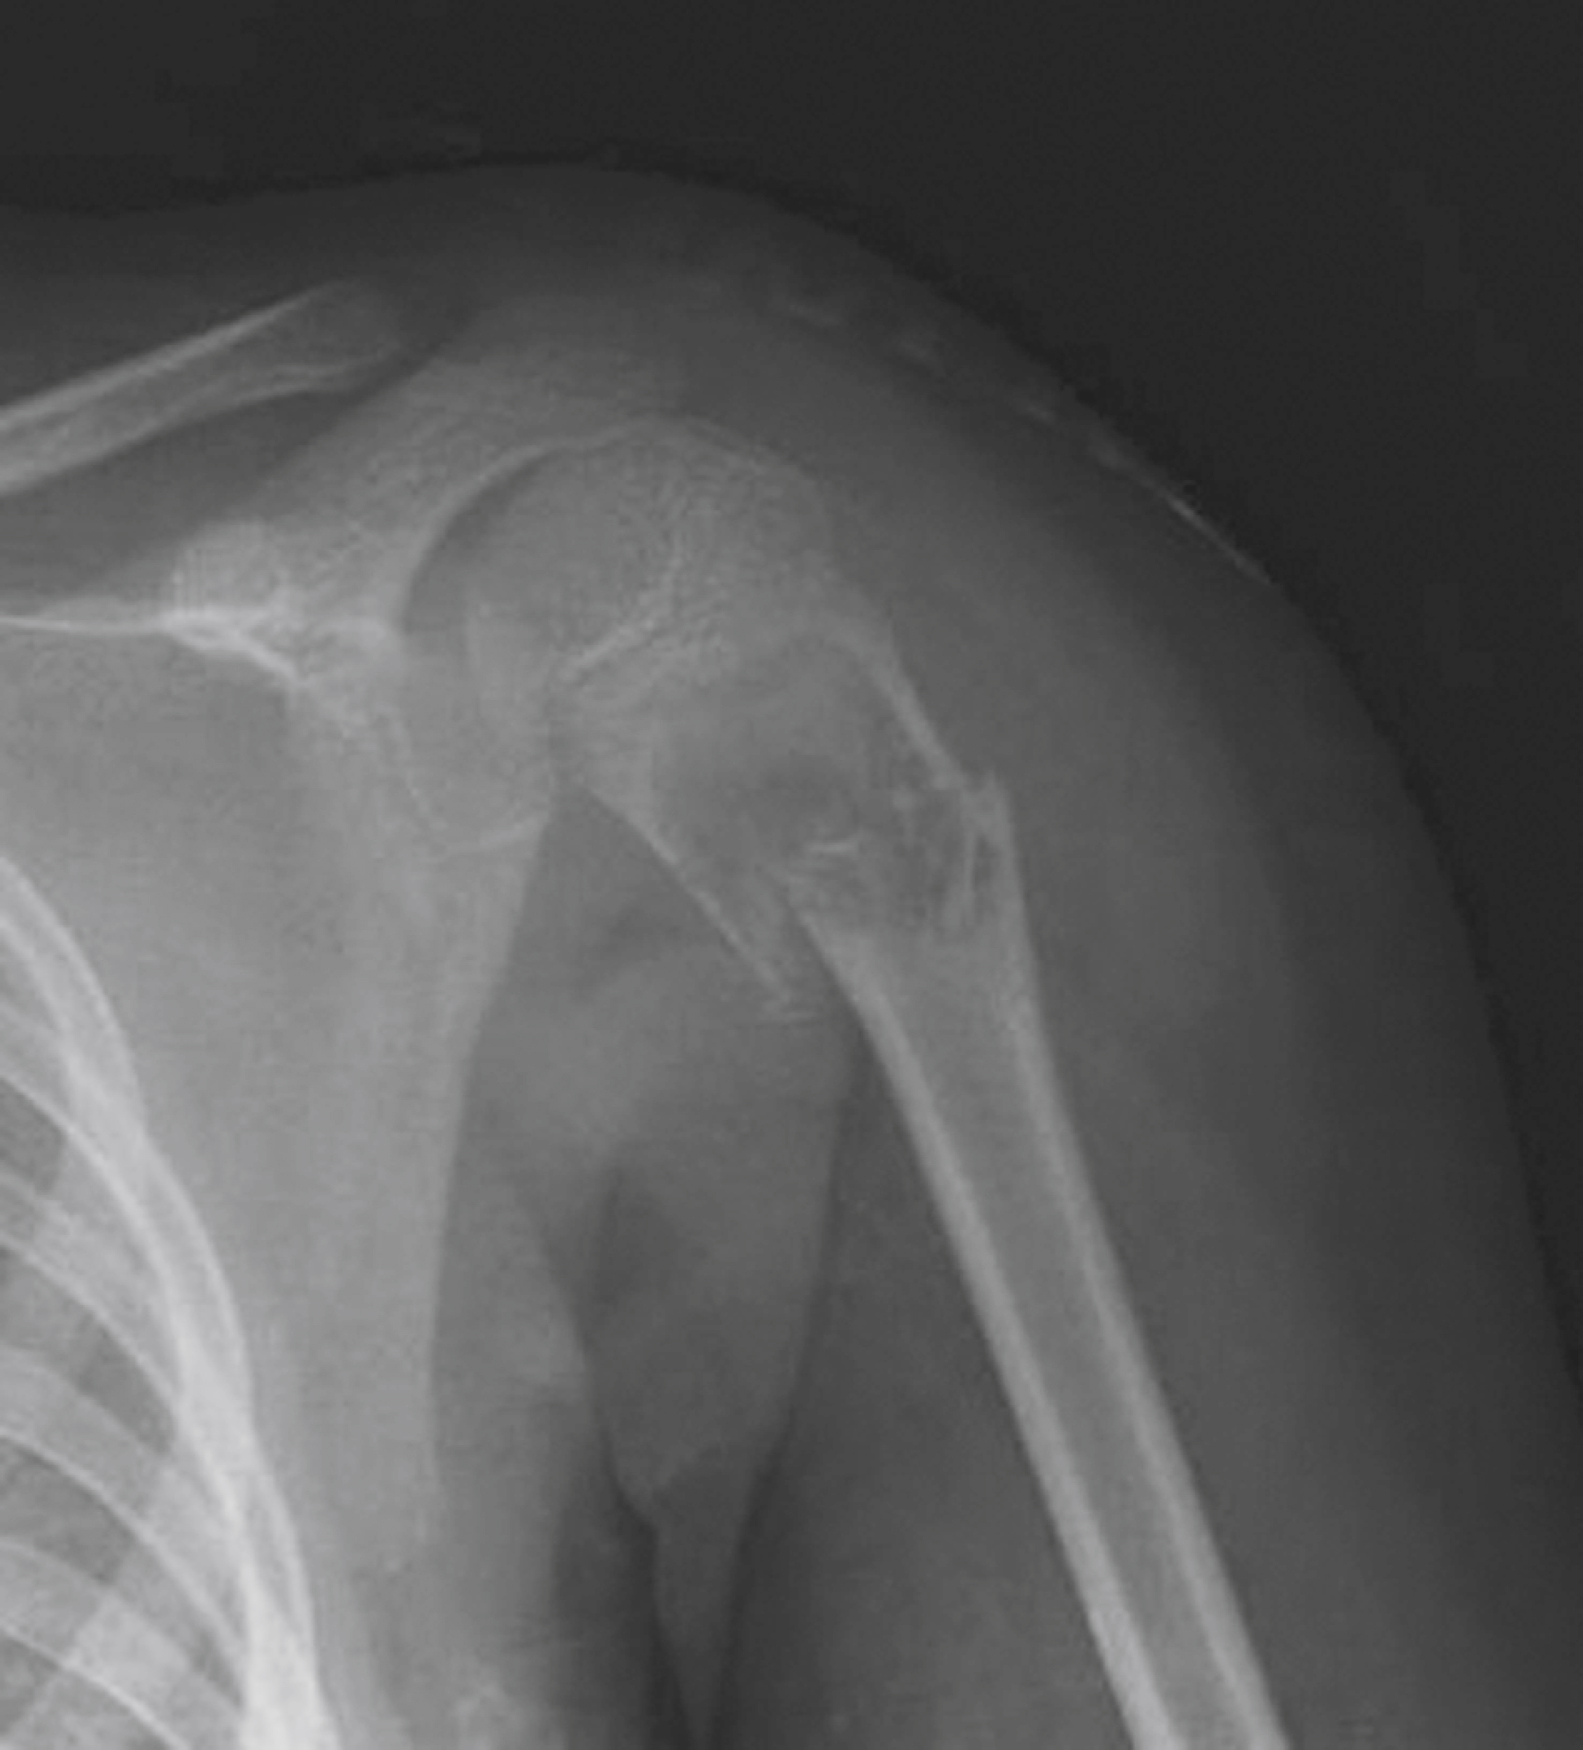

Diagnostic testing for humeral shaft fractures

Imaging studies should routinely include the shoulder and elbow joints. The humerus is a common site for benign tumors, unicameral cysts, and primary bone malignancies, as well as a common site for metastatic disease. Thinning of the cortex and abnormal osteoblastic or osteoclastic activity are evidence of a pathologic fracture ( Fig. 44.6 ). Pathologic lesions may require orthopedic surgical intervention, though once a fracture occurs, a multidisciplinary approach with oncology should occur to determine the best course of surgical intervention. While these fractures may be stabilized with treatment such as plates, pins, intramedullary nails, cement, and joint replacement, these underlying fractures do not heal well without concomitant treatment of the underlying pathologic condition.

Pathologic Fracture of Proximal Humerus.